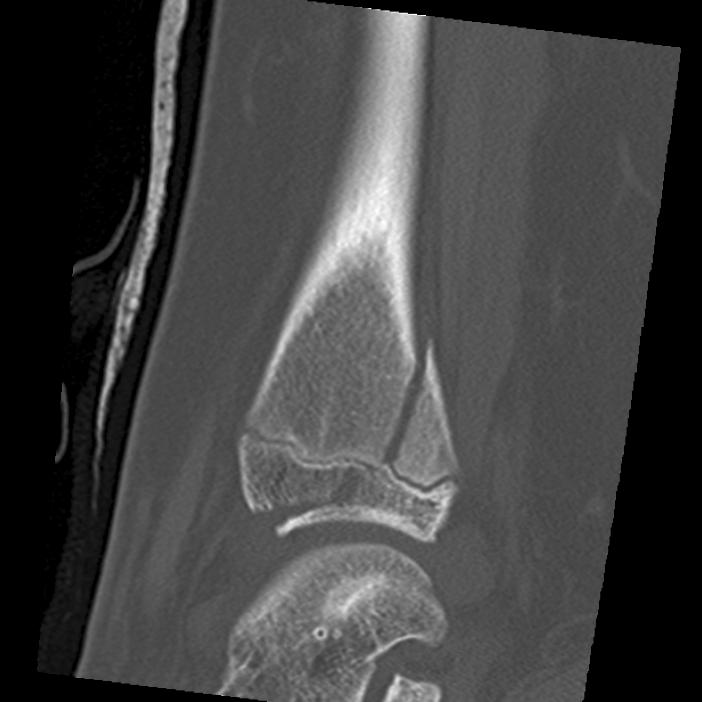

Triplanar Fracture

Definition

- fracture in coronal, sagittal and transverse planes

- 2, 3 or 4 part

Xray

Type III / Tillaux on AP

Type II on lateral

CT

Type III on coronal

Type II on sagittal

3 point star on axial